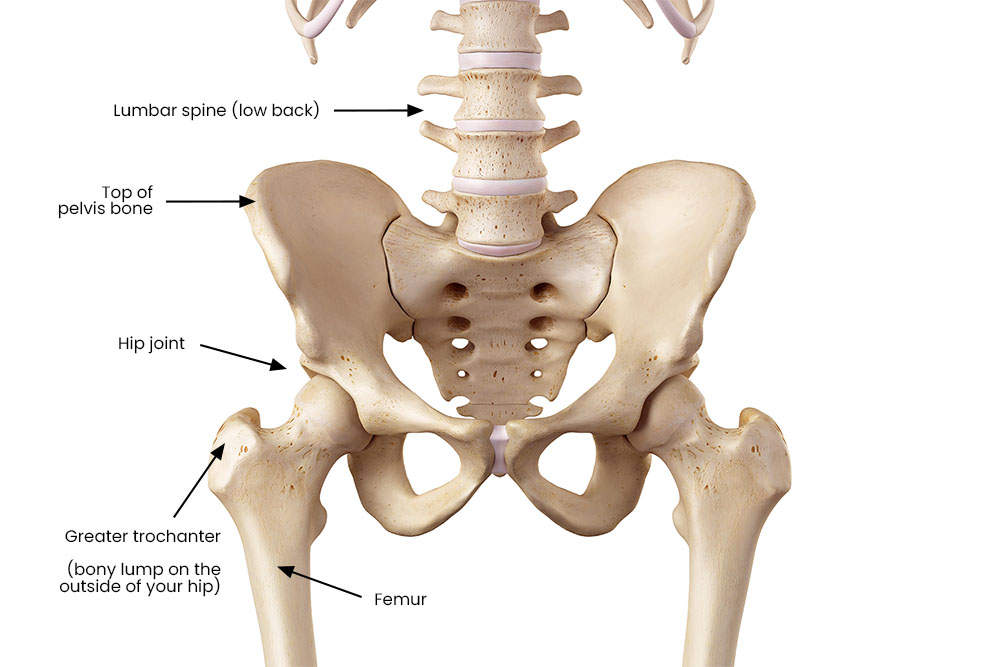

Your hip joint is a ball and socket joint between your pelvis and your thigh bone (femur). It has very strong ligaments holding it together, including one deep inside the joint. That is why dislocations are rare and need a very strong force to happen, such as a motorbike accident.

As well as bones, muscles, ligaments and tendons, your hip joint has:

- a capsule that surrounds it

- a labrum (rim of cartilage) to make the socket deeper

- bursae (fluid-filled sacs) to protect the tendons and muscles when they move against your bones.